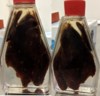

Kinyoun and Ziehl Neelsen

The oocysts are purple red colour or whiteish

Can have thick or thin wall

Cryptosporidium Parvum (oocyst)

Ziegl Nelsen staining

Cryptosporidium Parvum